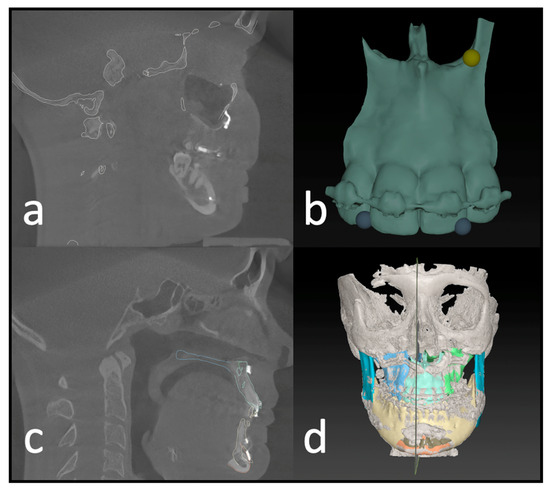

Previous studies have rarely shown increased risks of complications with additional maxillary multipartition compared to standard Le Fort I osteotomy [10]. The procedure can eliminate the burden of a preceding surgery (SARPE) if the indication is given, and the transversal development is moderate. The indication for maxillary multipartition is mainly found in transversal deficits up to 6–7 mm. In rare cases, correcting the transversal ratios or asymmetry of the alveolar crest may be necessary even after SARPE. In segmental maxillary osteotomies, a distinction is made between the two-piece maxilla (medial split), three-piece maxilla (Y-cut or H-cut), and asymmetrical modifications. Performing these osteotomies requires more extensive preoperative planning (Figure 1) and a thorough surgical approach that is often more time-consuming in theatre. Additional osteosynthesis and measures, such as splints with wiring, are required to increase stability. As the risk of transversal collapse is always given in segmented maxillary osteotomies, prolongated splint use with palatal extensions or wiring has been described and widely used.

With multisegmented maxillae, the patient requires longer retention to ensure long-term stability, as there is always a risk of transversal collapse or instability. The rigidity of the patient-specific implant allows better position-finding and promises higher dimensional stability. Full arch designs can eliminate the need for additional osteosynthesis between segments (Figure 1d). The virtually designed implants are based on interconnected L-plates.

Figure 1. (a) Depiction of the roots to indicate the ideal plane for the osteotomy. (b) Virtually planned “three-piece maxilla” to compensate for transversal deficit and close the anterior open bite. (c) Marking and drilling guide: slots mark the osteotomy between canines and lateral incisors. The smaller drilling holes are for the fixation of the guide; the larger holes will hold a metal sleeve to guide the holes for the PSI fixation. (d) 3D design of the patient-specific implant with cranial stabilization bars, which can later be removed.